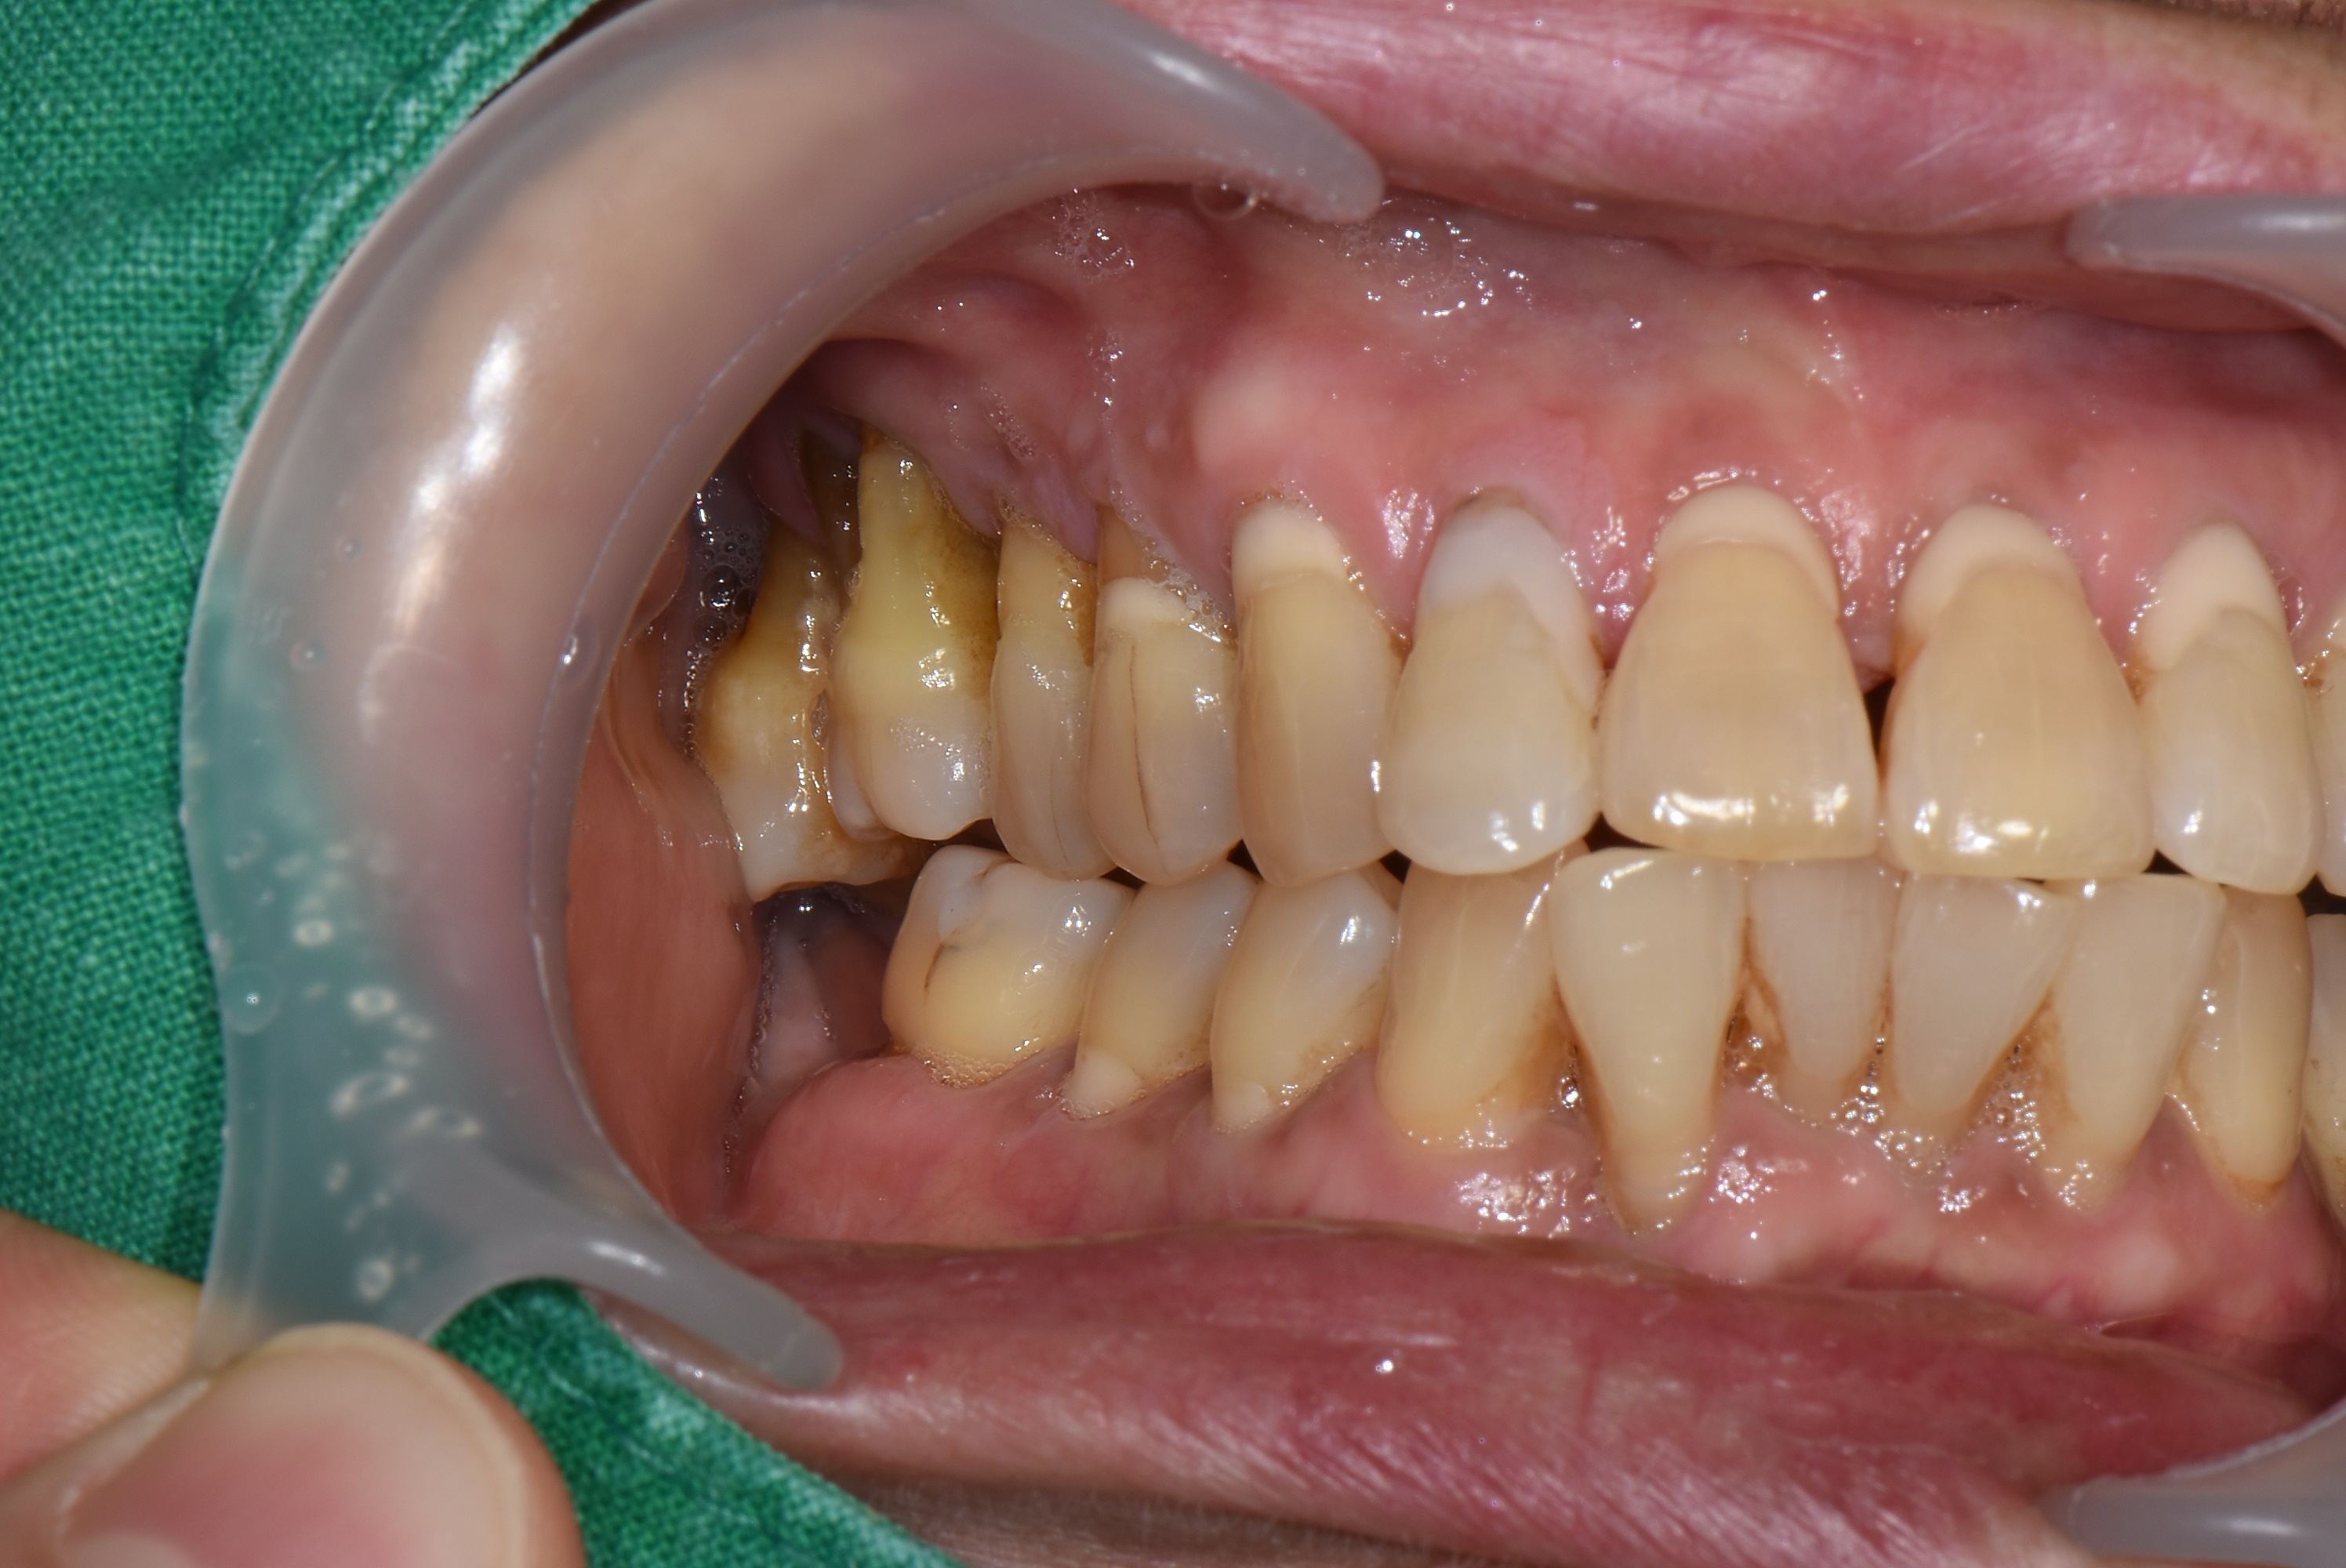

검진을 해보니 위에 양쪽 어금니가 많이 내려와 있고 치주염이 심하여 흔들리고 있었습니다.

치아를 살리기에는 이미 늦은 상태로 발치 후 임플란트로 치료 계획을 세웠습니다.

파노라마 엑스레이와 구내 사진에서 보듯이 위에 양쪽 어금니는 모두 발치가 필요한 상태입니다.